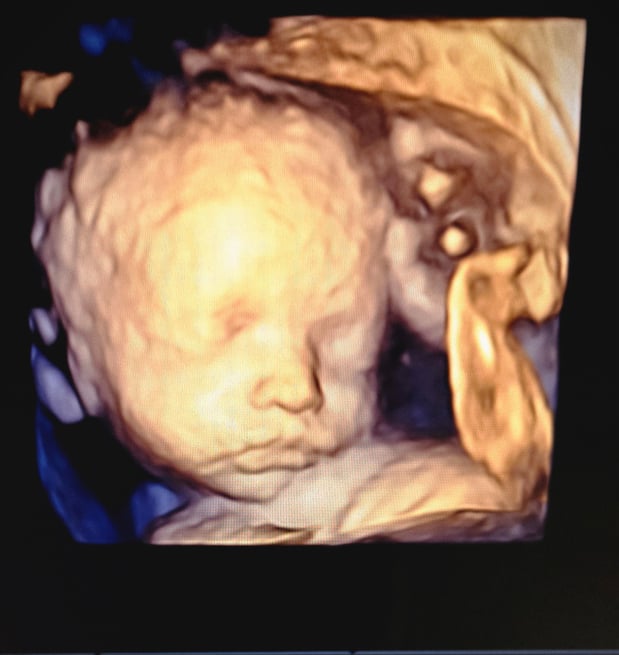

Tasha Crump, is registered by the American Registry of Diagnostic Medical Sonographers (ARDMS) and have over 18 years experience in medical diagnostic sonography specializing in Maternal Fetal Medicine. She is a highly proficient in the art of 3D 4D ultrasound. Tasha has practiced and trained in NYC's top ranked hospitals including Columbia Presbyterian. At Love at First Sight Imaging Studio you'll be in a very comfortable and calming atmosphere for you and your family to bond with your baby. We have state of the art equipment with HD Live to image unbelievably realistic views of your baby. You will fall in Love at First Sight.